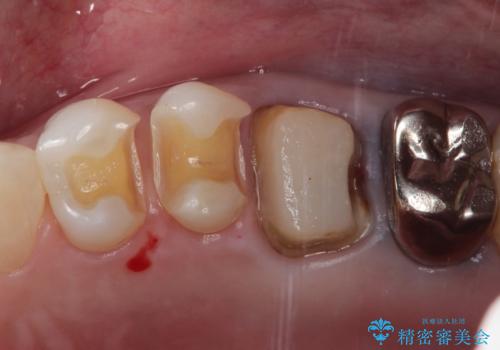

過去に装着されたメタルインレーを除去したのち、内部の虫歯を除去、セラミックインレーにて修復治療を行なっております。

e-maxプレスインレーを用いることで、高い精度と強度を達成することができました。